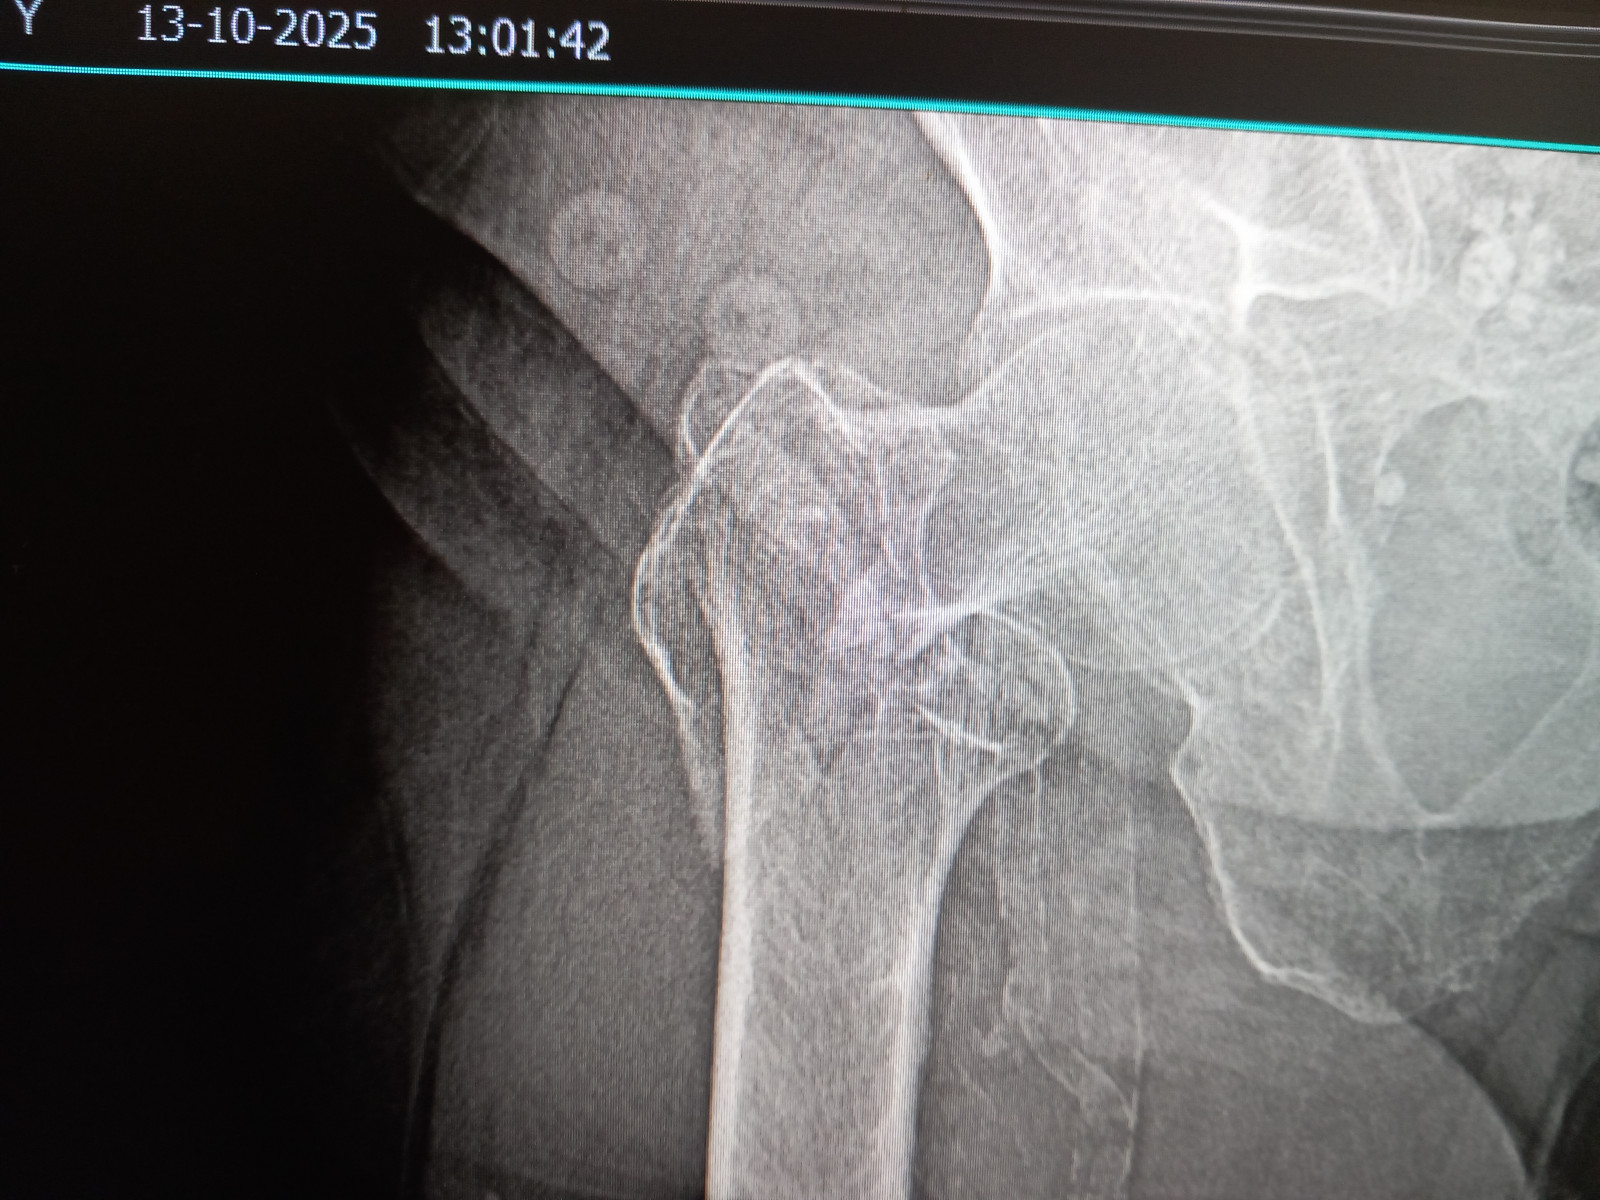

Перелом бедра